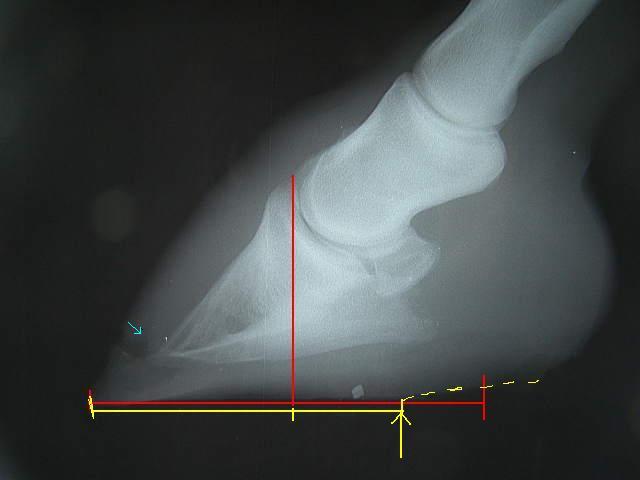

今回の左前肢

ラメラーウェッジがだいぶ取り除かれ、蹄が蹄壁にきちんとくっついて生えてきているのが確認できてホッとしました。

前回の装蹄後から左前肢の歩様がおかしかったのは、削り取った蹄の下端が先端のラメラーウェッジを押しているか、蹄尖部に重心がかかるようになっているのがちょっと痛いのではないか、とのこと。

ヒールアップに関して、蹄壁と蹄底の角度を測ってくれました。

前回は65°。

パットをフラットなものにしたら62°。

3°の変化でも本人にとっては大きく変化したようで、だいぶ軽快に肢を運ぶようになりました。